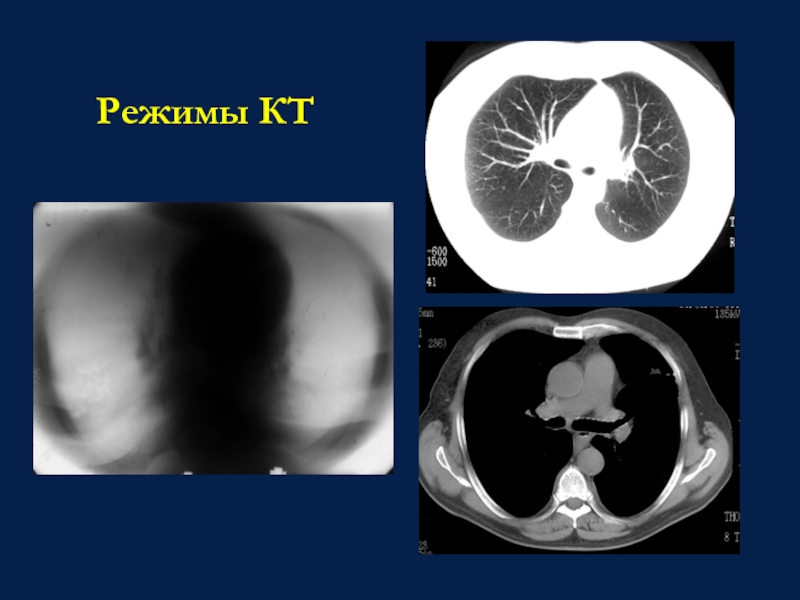

Слайд 20Режимы КТ

Режимы КТ

Слайд 18Отсутствие суперпозиционности;

Поперечная ориентация слоя;

Высокое контрастное разрешение;

Определение коэффициента поглощения;

Различные виды обработки

изображения.

Рентгеновская компьютерная томография

Особенности КТ-изображения:

Отсутствие суперпозиционности;Поперечная ориентация слоя;Высокое контрастное разрешение;Определение коэффициента поглощения;Различные виды обработки изображения.Рентгеновская компьютерная томографияОсобенности КТ-изображения: